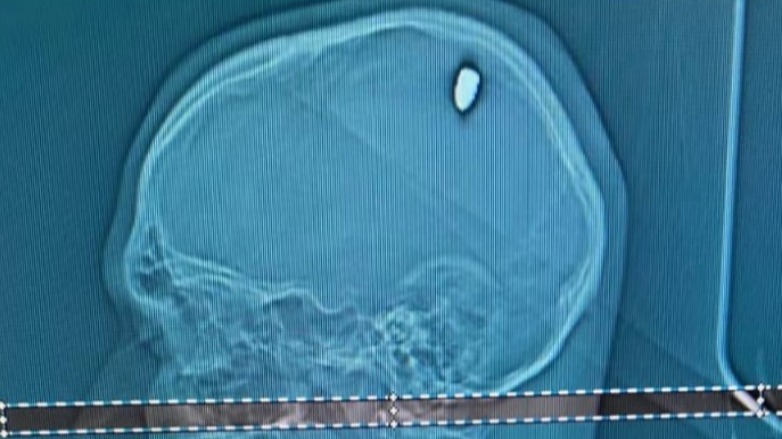

Après quatre jours de gueule de bois, un étudiant brésilien découvre qu'une balle de 9mm était en fait venue se loger dans son crâne le soir du nouvel-An.

C'est pour le moins... peu commun. Un étudiant brésilien a été hospitalisé quelques jours après le nouvel An, se plaignant de maux de tête continus depuis une soirée très arrosée. Le jeune homme, après avoir consulté un médecin, a en fait découvert que sa douleur provenait d'une balle de 9mm venue se loger dans sa tête.

"Une partie de la balle a pénétré dans son cerveau, provoquant une compression dans cette zone et des mouvements involontaires dans son bras. Si elle avait été quelques millimètres plus profond, la situation aurait pu être plus grave", a précisé un médecin. L'opération sur la tête du jeune homme s'est, heureusement, bien déroulée. Une enquête a tout de même été ouverte pour comprendre d'où vient le projectile et comment il a atterri ici.